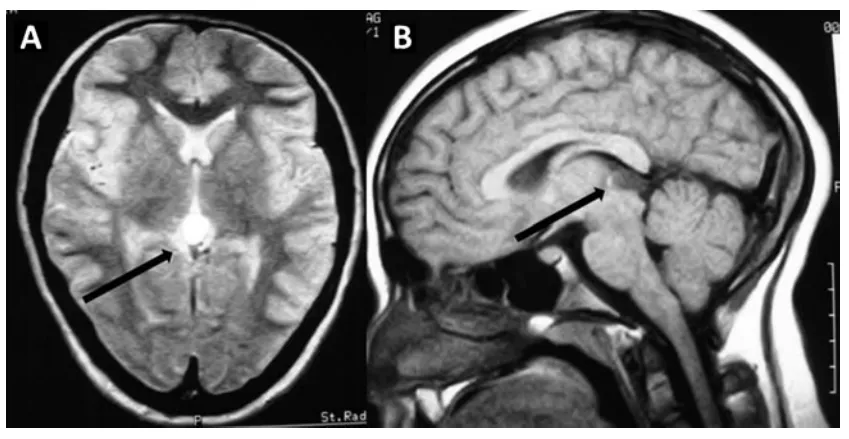

松果体解剖位置极其关键,位于间脑顶部的大脑中心区域,毗邻...

松果体肿瘤作为一类起源于颅内松果体区的罕见病变,因其位置...